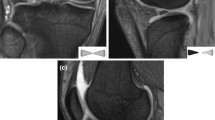

Bone bruising, impaction fractures, and Segond fracture

Bone bruising was observed in 236 patients (92.9%). The injury patterns were as follows: pivot shift (Fig. 8) (184 patients, 78%) and other (52 patients, 22%). Dashboard or hyperextension patterns were not observed. Additionally, MFC and PMT bone bruising (Fig. 9) were observed in 48 (18.9%) and 100 (39.4%) patients, respectively.

Impaction fractures of the LFC and PLT (Fig. 10) were identified in 116 (45.7%) and 12 (4.7%) patients, respectively. Nineteen (7.5%) patients had Segond fractures (Fig. 11).

Bone bruising was observed in most patients (92.9%). The most frequent pattern (78% of patients) was the pivot-shift pattern (bone marrow edema in the posterolateral area of the lateral tibial plateau and central area of the LFC). This might be explained by the fact that most ACL injuries and the pivot-shift bone-bruising pattern share the same trauma mechanism [flexion valgus and external rotation (pivot-shift)] [19, 51, 52]. It is hypothesized that, during the pivot shift mechanism, the posterolateral aspect of the lateral tibial plateau subluxates anteriorly and impinges with the central part of the LFC [19, 21]. In line with the present study, Yoon et al. [21] reported a high prevalence (84%) of bone bruising in patients with ACL injuries (MRI performed within 6 weeks of the trauma), with most bone bruising occurring in the LFC (68%) and the lateral tibial plateau (73%). These findings support the hypothesis that bone bruising should be interpreted as a footprint of the mechanism of injury [19]. Impaction fractures in the LFC and PLT (present in 45.7% and 4.7% of the patients, respectively) can also be observed in the context of a pivot-shift mechanism [19, 53]. Interestingly, these impaction fractures are associated with progressive cartilage degeneration, greater anterolateral rotatory laxity, and poorer postoperative outcomes [23, 24]. Bone bruising was also commonly observed in the MFC and PMT (18.9% and 39.4%, respectively). It has been hypothesized that bone bruising in the medial compartment occurs as the result of a contrecoup mechanism. If energy trauma is not dissipated by the initial pivot-shift mechanism, a contrecoup injury with impaction of the MFC and PMT may occur as a result of sudden tibial reduction with compensatory varus alignment and internal tibial rotation [52]. However, we previously reported a strong association between MFC bone bruising and dMCL injuries in the same patient cohort from the NACOX study [2]. We hypothesized that the avulsion of the meniscofemoral ligament from the MFC may be responsible for bone bruising in the MFC. PMT bone bruising has been strongly associated with MM ramp lesions [1] as they probably share the same trauma mechanism [1, 54].